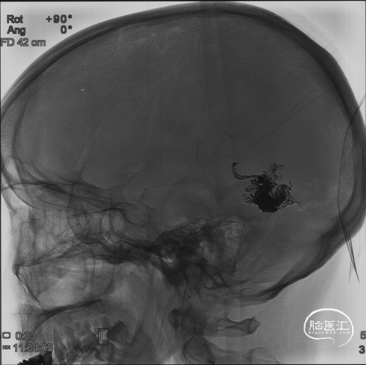

再超选左侧MMA,Echelon-10微导管及Marathon微导管分别在Hybrid 0.008微导丝导引下经MMA分支超选接近畸形团

Echelon-10在Marathon微导管近端填圈做“塞子”,暂时不解脱

经Marathon造影显示导管头位置及畸形团构筑

经Marathon缓慢推注Onyx 18,Onyx在畸形团内弥散良好,并进入引流静脉

停顿后进一步注射Onyx,此时弥散进入周边残余病灶,直至完全充盈整个畸形团和引流静脉

在Echelon-10和弹簧圈支撑下拔除Marathon微导管,血管无明显移位,随后解脱弹簧圈,撤出Echelon10微导管,造影显示无畸形残留